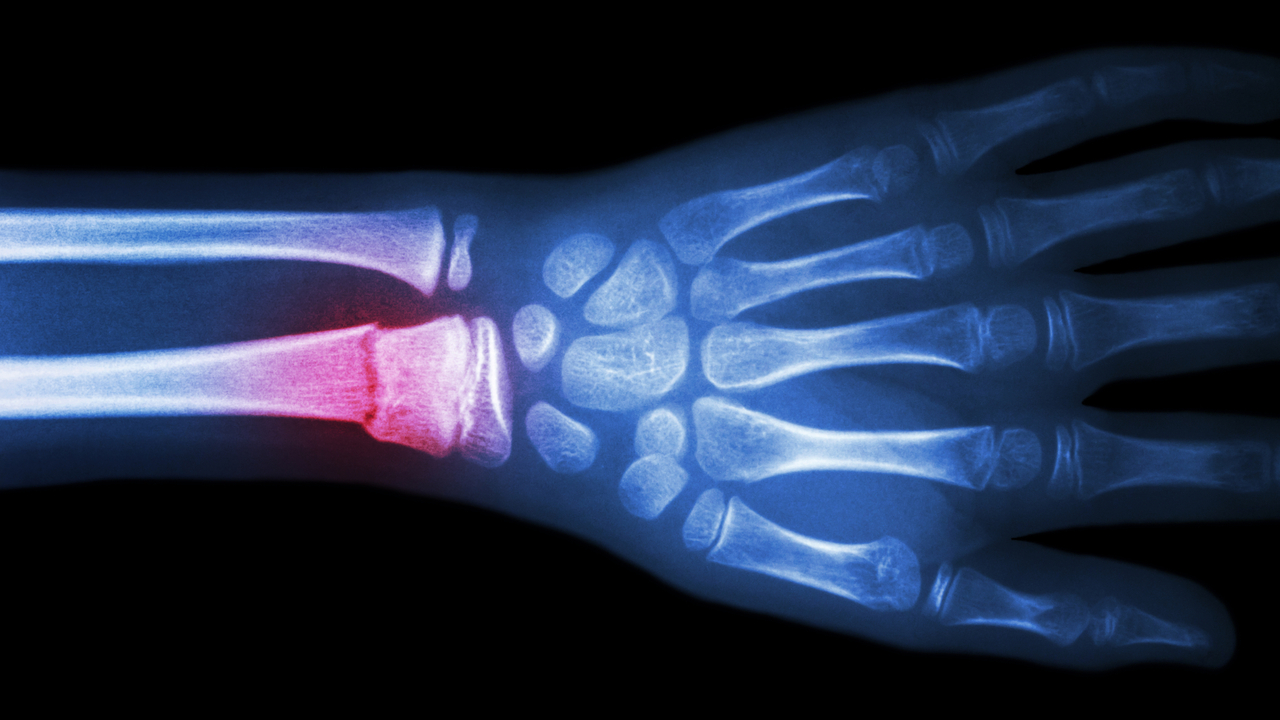

Now cryotherapy – exposure to cold – is widely used in surgery (for example, in the fight against cancer), physiotherapy and preservation. Cooling inhibits swelling and reduces pain because temperature changes affect nerve cells, reduce inflammation and increase local immune potential. However, there is no practical way to treat bones with this method.

Six weeks later, the two groups were compared. It turned out that the fastest recovery occurred in the group in which cryotherapy was most frequently applied. At the same time, cryotherapy affected untreated limbs – the dynamics of bone restoration was significantly better than in the control group (paws were not cooled in such rats). This is because exposure to cold affects not only bone cells and blood vessels at the defect site, but also immune cells in the surrounding tissues and area, according to scientists described in an article in the Journal of Thermal Biology. body as a whole.

At the same time, the researchers warn: There’s no reason to say that cryotherapy will heal fractures faster in humans, too. Soft tissue thickness in humans differs from that in rats, and the instrument used is likely to require modifications for use in humans. Experts assure that preclinical studies will continue.